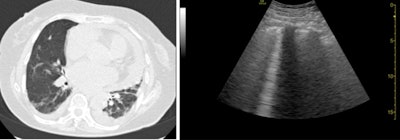

Septal thickening and pleural-pericardial effusion on CT (left). B-lines on ultrasound (right).

Septal thickening and pleural-pericardial effusion on CT (left). B-lines on ultrasound (right).Out of the 51 patients in the study, 37 patients had findings suggestive of COVID-19 on CT and 40 had COVID-19-like findings on ultrasound. Statistical analysis revealed significant agreement between lung ultrasound and CT findings, including an ultrasound sensitivity of 100%, specificity of 79%, and positive predictive value of 93%.